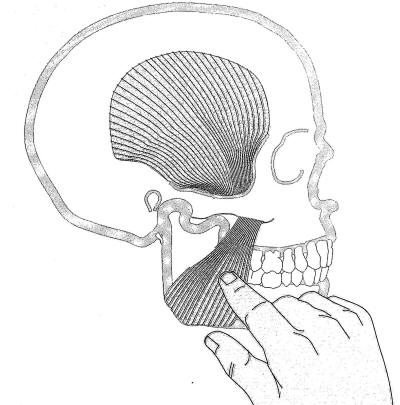

Palpación del músculo masetero: |

|

La palpación del músculo masetero no presenta

inconvenientes, con una presión moderada en apertura y

cierre podremos determinar el grado de dolor que presenta el

paciente y el trismus presente. |